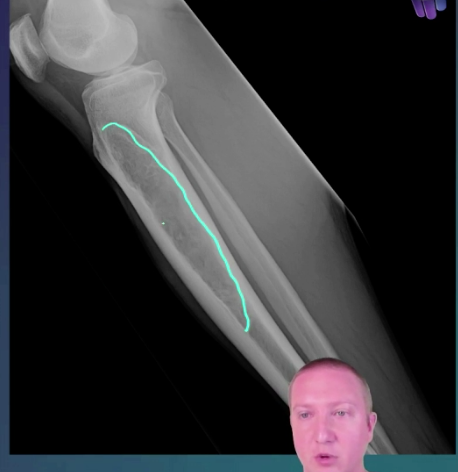

Osteofibrous dysplasia * benign fibro-osseous cortical lesion * occurs almost exclusively in the tibia and fibula. * It is most commonly seen in the mid-diaphysis of the tibia. * Terminology * A commonly used synonym is ossifying fibroma of the long bones. * Epidemiology * most common in younger patients, e.g. ~ 10 years of age * less commonly reported in older patients, up to 63 years of age 3 * slight male predilection (3:2 ratio 3) * Clinical presentation * Most patients present with pain and swelling, and patients may present secondary to a pathological fracture. * Pathology * Osteofibrous dysplasia is considered as a benign, non-neoplastic condition. Some consider it as part of a spectrum of osteofibrous dysplasia-like adamantinoma and adamantinoma. * Microscopic appearance * Histology shows trabecular bone woven within fibrous stroma with osteoblastic rimming and mature lamellar bone. * It is closely related to fibrous dysplasia (fibrous dysplasia is predominantly medullary), but the zonal phenomenon and osteoblastic rimming of bony trabeculae are absent in fibrous dysplasia. * Osteofibrous dysplasia and ossifying fibroma of the jaw have similar histological characteristics, but osteofibrous dysplasia shows cytokeratin-positive cells, whereas ossifying fibroma of the jaw shows psammomatous calcification, which are exclusive features. * Although adamantinoma can contain osteofibrous dysplasia-like components, nests or strands of an epithelioid cell are the differentiating feature between adamantinoma and osteofibrous dysplasia. * Adamantinoma with scarce epithelioid component and mostly composed of osteofibrous dysplasia-like tissue are considered as osteofibrous dysplasia-like adamantinoma. * Radiographic features * Osteofibrous dysplasia is classically a lytic lesion centred in the tibial cortex, often with sclerotic margins. * Because of its similarity to adamantinoma, a much more aggressive pathology, a primary issue is differentiating between the two. * Due to intralesional heterogeneity, needle biopsy may result in diagnostic misclassification, particularly with underestimation of aggressive lesions. Thus, radiologic-pathologic correlation is important with benign or equivocal biopsy results 3. * Osteofibrous dysplasia tends to be: * smaller (mean 6-7 cm versus 10-17 cm for adamantinoma) * with more distinct margins * less likely to involve the medullary cavity * Plain radiograph * Plain radiograph remains the initial and chief investigation. * location: * along long axis: mid-diaphysis, especially anteriorly * along transverse axis: cortical with medullary encroachment * consistency * lucent or ground-glass * lobular-to-bubbly in appearance * margins * narrow zone of transition * sclerosis common * no nidus * no aggressive periosteal reaction * benign-appearing periosteal reaction is non-specific, and can be seen in all lesions along the osteofibrous dysplasia/adamantinoma spectrum 3 * +/- pseudotrabeculation and anterior bowing * MRI * MRI is helpful in evaluation of suspected osteofibrous dysplasia, particularly to evaluate the extent of intramedullary involvement. Complete medullary cavity involvement is more suggestive of adamantinoma. * T1: intermediate signal * T2: intermediate-to-high signal * T1C+: diffuse and intense enhancement. * +/- soft tissue component (non-specific) * can be seen in all lesions along the osteofibrous dysplasia/adamantinoma spectrum 3 * no aggressive cortical destruction * Treatment and prognosis * Surgery is reserved for lesions that are large or demonstrate aggressive behaviour. * They usually have an excellent prognosis and usually, stabilise or spontaneously regress once the child is over 10 years old. * It can be locally destructive and may result in pathological fracture, subsequently pseudarthrosis. * Local recurrences can occur after surgery with some aggressive recurrence, possibly due to components of adamantinoma or possible transformation to adamantinoma. * Differential diagnosis * Consider * ossifying fibroma * adamantinoma * osteofibrous dysplasia-like adamantinoma * intracortical fibrous dysplasia